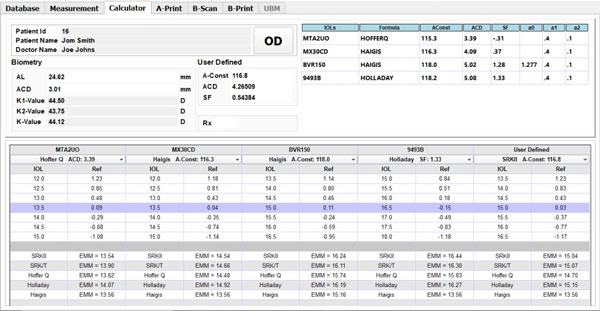

A-Scan

- The A-Scan part of the system performs intraocular distance measurements in seconds using contact or immersion method in either automatic or manual mode.